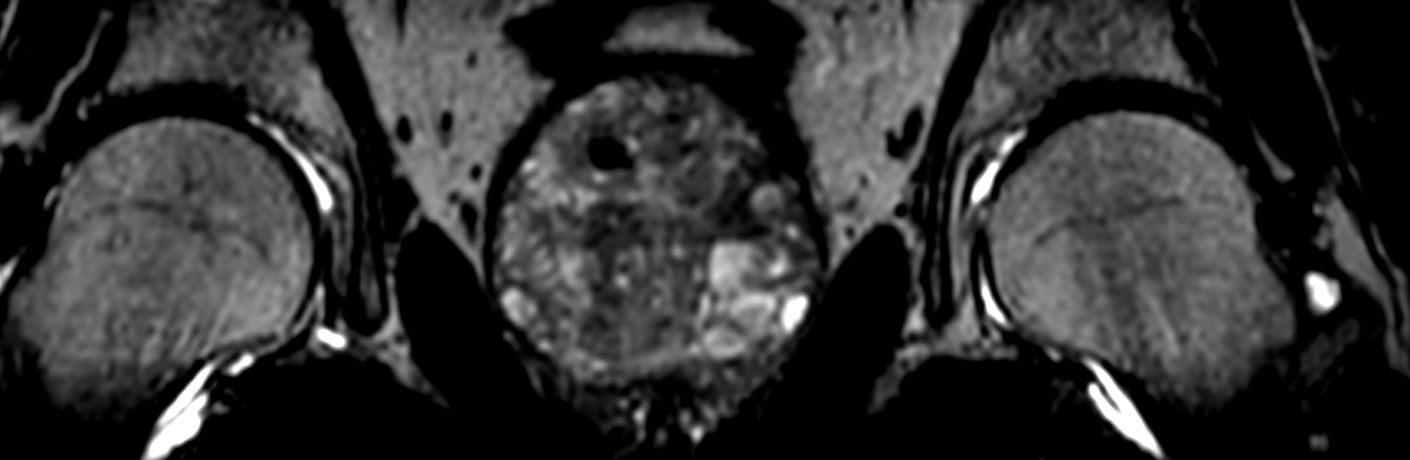

DWI b1000

DWI b1000 (ADC)